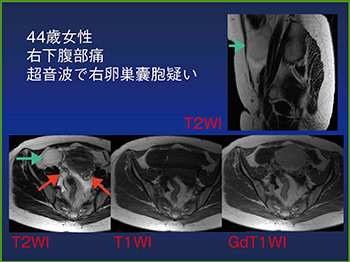

また,右下腹部痛で超音波検査の結果,卵巣腫瘍と診断された症例のMRIでは,T2強調で均一な高信号,T1強調で低信号を呈する囊胞性の腫瘤が認められた。しかし,同側に卵巣が確認されたため,虫垂の粘液瘤であることがわかった(図9)。

図9 超音波で卵巣囊胞が疑われた虫垂粘液瘤のMRI

卵巣腫瘍と間違いやすいこれらの疾患を見分けるためには,まず同側の卵巣を確認する。また,栄養動脈や導出静脈,周囲臓器との位置関係を確認することと,類似病変の存在を念頭に置いておくことで,誤診を防ぐことができる。